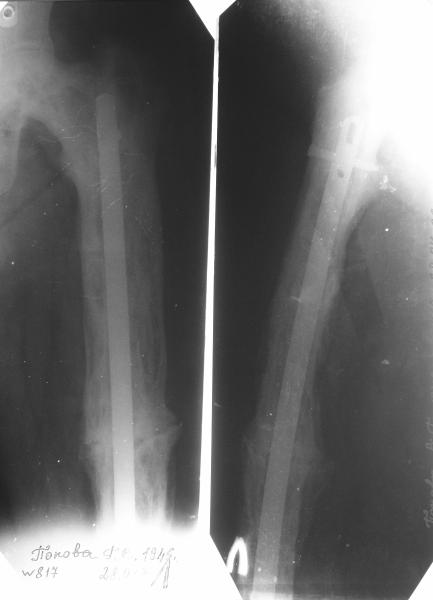

бывали ли у кого-нибудь такие случаи Уважаемые коллеги, вчера прооперировал женщину 60 лет с болезнью Педжета, переломом верхней трети бедра. Выявлена в августе этого года, сломала три дня назад от небольшого усилия. Из сопутствующих болезней лейкоз, сахарный диабет. Бывали ли кого-нибудь такие случаи, чем это все заканчивалось?

Пациент 82 лет, поступил через 5 мес. с несросшимся переломом после открытого интрамедуллярного остеосинтеза. Выполнили реостеосинтез стержнем 12 мм. ( мах. доступного нам в 2003 г.) Через 4 мес динамизация. В течении 2х лет сращения нет, тем не менее конечность опорна (ходит с тростью). От очередного реостеосинтеза отказались из-за сопутств. патологии.

PS: случай конечно не аналогичный, учитывая первичный открытый остеосинтез.